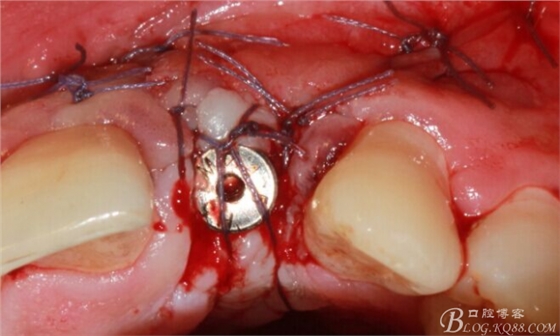

于是我果斷告知患者,手術(shù)失敗了,不能拖延,如不及時(shí)處理,炎癥繼續(xù)發(fā)展會(huì)很快波及鄰牙牙槽骨。患者接受我的建議。切開翻瓣,骨粉及生物膜消失了,骨吸收嚴(yán)重,幸運(yùn)的是,因?yàn)樘幚砑皶r(shí),鄰牙骨支持依然存在。

徹底掻刮。

有老師問我,為什么不在此時(shí)同期植骨同期植入植體?我的觀點(diǎn)是:不要一次做太多事情,做得越多風(fēng)險(xiǎn)越高。再說,此時(shí)軟組織不健康,沒有健康的軟組織如何能保證GBR的成功?所以,我僅放了一塊膠原蛋白就縫上了。